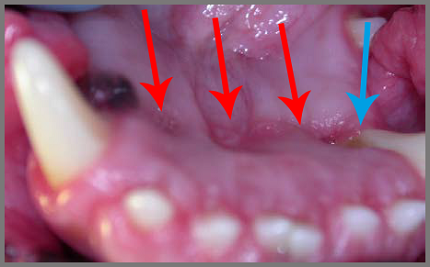

Op de volgende foto is te zien dat kiezen en tanden in het tandvlees prikken, waardoor ontstekingen en pijn de kop opsteken (rode pijlen). Achter de scheefstaande tanden blijft vuil zitten (blauwe pijl). Het vuil zorgt voor tandvleesontsteking en tandsteenvorming, wat de hond veel pijn geeft.